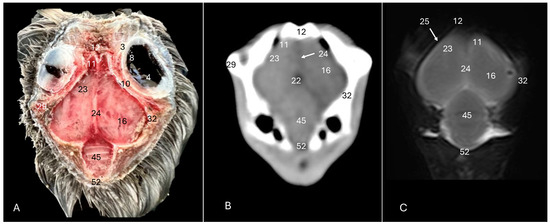

3. Result

3.1. Anatomical Sections

3.2. Computed Tomography (CT)

3.3. Magnetic Resonance Imaging (MRI)